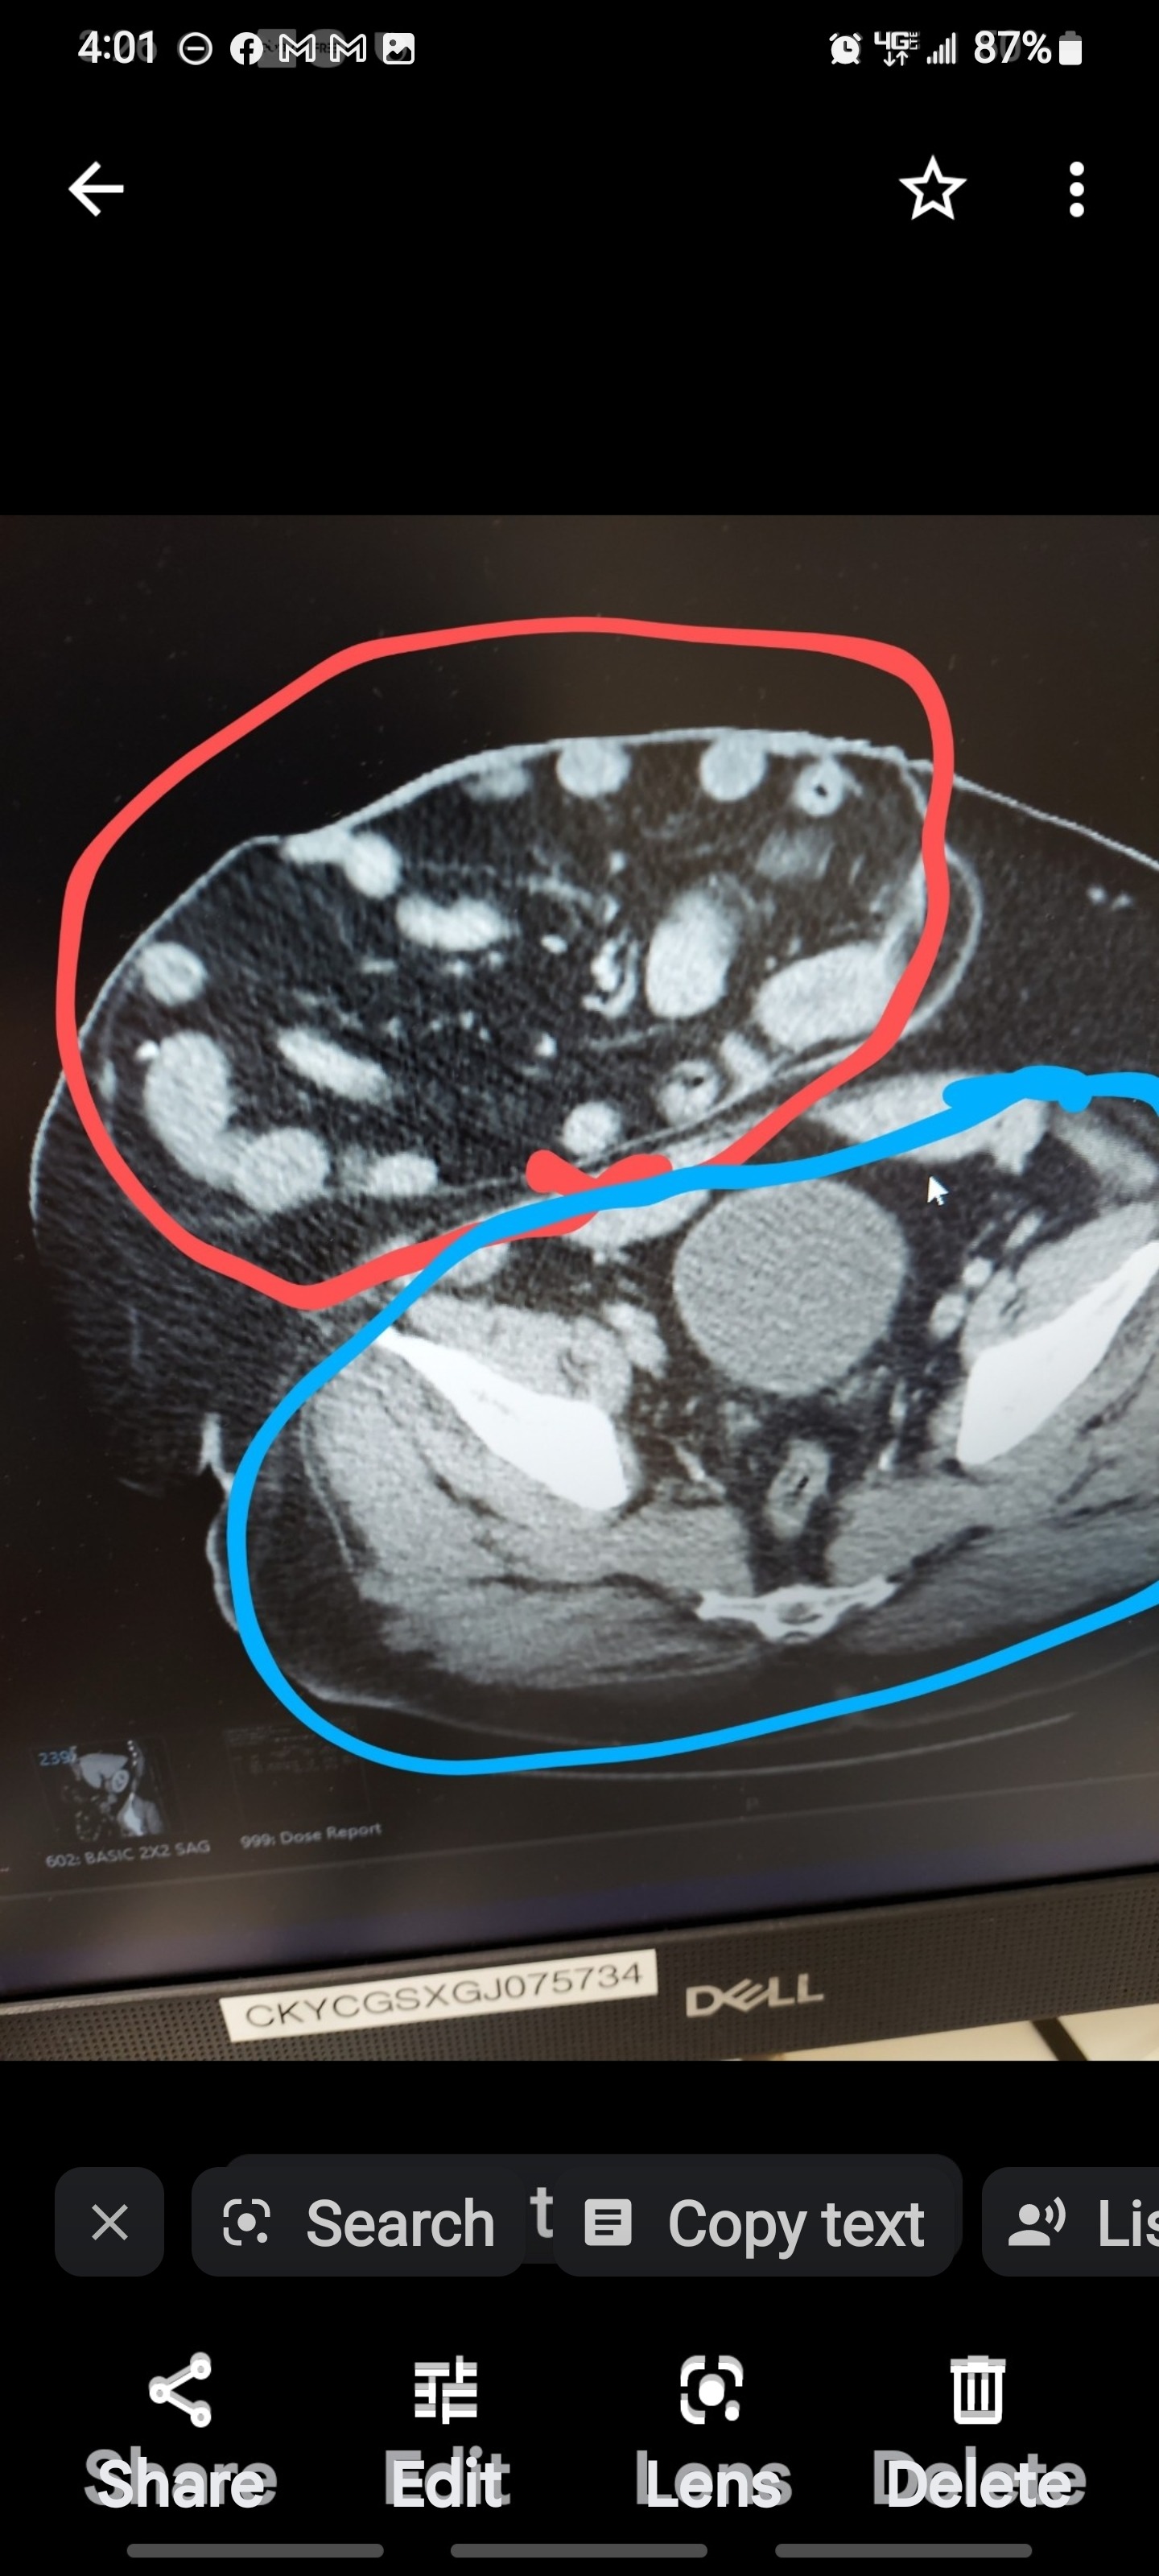

My name is Luc, and for the past eight years, I've been living with a surgical hernia. Because it's gone untreated for so long, I'm now facing additional health complications that make daily life even more challenging. On top of my health struggles, I recently went to eviction court and learned that I'll need to find a new place to live soon. It's been overwhelming trying to manage my health while also worrying about where I'll be able to call home next.